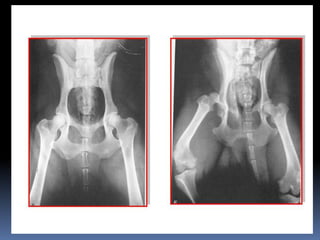

Doc, Me tragué una pelota

Doc, Me traguéuna pelota